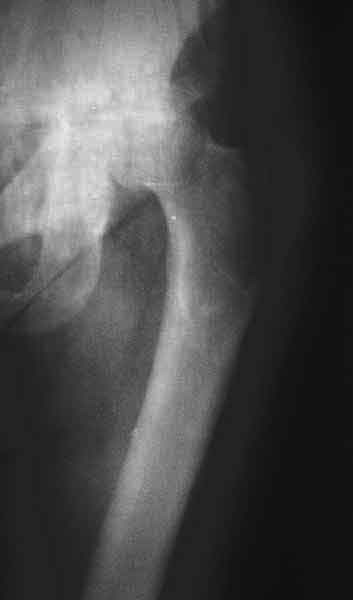

AV> опираясь на стул. На ногу не наступает. Укорочение 8 см. Иногда

А за счет чего такое укорочение? По снимку не видно соответствующего дефекта. Ну плюс приводящая контрактура - но все равно как-то уж больно много. Может, сделать снимки и таза обзорный с обоими проксимальными отделами бедра, и коенный суставов с приложенной линейкой какой?

Судя по снимку, максимум истинное укорочение около 4 см, что может быть коррегировано интраоперационно. Вопрос в другом: куда ставить ацетабулярный компонент в истинную или во вновь сформированную ( впадина диспластичная).

По рентгенограммам укорочение не более 4 см, остальное возможно за счет контрактуры. Опыта с низведением аппаратом Илизарова нет, но мы одномоментно такие укорочения корригировали вполне успешно (в год 5-10 именно таких и проходит). Лишние этапы пожалуй только будут способствовать инфекции. Доступ чаше применяем передне-наружный, а вот протез наверное поставили бы здесь на цементе - остеопороз выражен.

The X ray that you provided does not show 8 cm of shortening. Perhaps you could send one showing the whole pelvis and proximal femurs.

I agree with Dr Eid's comments. The origin of the 8 cm leg length difference is a puzzle. Is this a clinical measurement? In that case contracture of the joint might affect the measurement. Can we see an AP pelvis to include both hip joints (including a calibration object with a known length) so that the difference in leg lengths that can be ascribed to the hip deformity and bony reabsorption can be measured. This sort of xray will help with templating for the TJR also. I would be very tempted to do a one stage procedure and accept some shortening. Shoe lifts should take care of a 3-4 cm difference.

До травмы проблем с ногой не было. Укорочения, болей и т.п. не отмечал. Сегодня перемерял укорочение - меньше 7 см намерять не

По уровню малых вертелов (с учетом рентгеновского увеличения) получается 5 см. Клинически ногу низвести путем тракции невозможно. Из движений - сгибание до 40*, остальные движения "символические".

Ортопедическое укорочение пострадавшей ноги может быть и 7, и 10 см. за счет контрактур в тазобедренном суставе, а вот истинное укорочение, судя по представленным рентгенограммам, вряд ли больше 4 см.